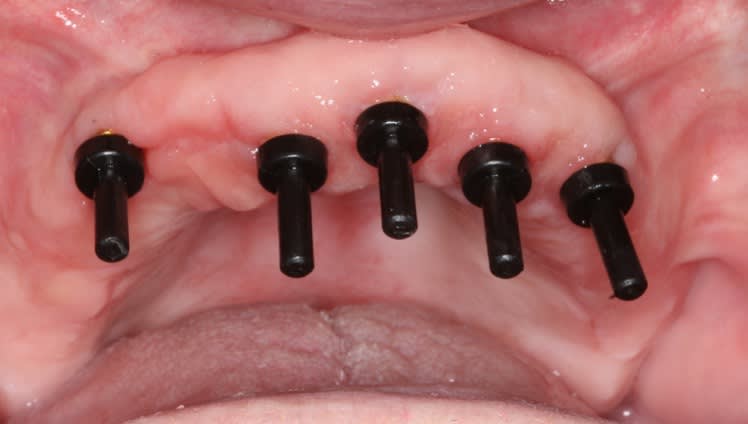

Due to the angulation of the implant placement, a 15-degree angled LOCATOR abutment was placed (Figure 5 and Figure 6). Angulation pins were passively placed into the LOCATOR abutments to determine proper spacing (Figure 7). The existing maxillary and mandibular appliances were scanned (fastcscan io™ with Medit® i700®, Glidewell) for the laboratory to design the initial try-in appliance prior to milling of the final zirconia LOCATOR FIXED® prosthesis (Figure 8). LOCATOR scan bodies were placed, and the LOCATOR level digital impression was made (Figure 9).

A polymethyl methacrylate (PMMA) appliance was verified for occlusion and esthetics (Figure 10). Once esthetics were evaluated and approved the final LOCATOR FIXED® prosthesis was processed in BruxZir zirconia (Glidewell). The black laboratory procession attachments were removed and replaced with the appropriate final LOCATOR FIXED® insert (Figure 11). The LOCATOR abutments and processing attachments are illustrated in Figure 12, which shows the tools for seating and removing the proprietary inserts and the insertion and removal tools. Proper inserts were selected and positioned per the manufacturer’s instructions (Figure 13). The final zirconia fixed prosthesis was seated using the seating tool and evaluated for stability (Figure 14). The prosthesis allowed for minimal palatal coverage, and the functional and esthetic maxillary reconstruction was complete (Figure 15 and Figure 16).